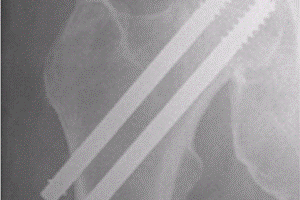

Lårhalsbrudd opereres på 2 ulike måter. Dersom bruddet står i pen stilling (lite forskutt) er det vanlig å operere bruddet med 2 pinner eller skruer (figur 2).

Lårhalsbrudd

Dersom bruddet står ute av stilling (mye forskutt) vil en hos yngre mennesker forsøke å sette bruddet på plass og operere det med 2 pinner eller skruer. Imidlertid er det en viss risiko for komplikasjoner etter en slik operasjon, for eksempel at bruddet ikke gror og at skruene løsner. Dette oppstår gjerne de første 6 månedene etter bruddet. En annen forekommende komplikasjon er sammenfall av lårhodet grunnet manglende blodforsyning til lårhodet. Dette merker pasientene ofte som økende smerter 6 – 18 måneder etter bruddet. Behandlingen for begge komplikasjoner er protese i hofteleddet. Kirurgen kan velge mellom en delprotese eller en totalprotese avhengig av tid fra første operasjon, pasientens alder og medisinske tilstand samt hofteleddets tilstand.